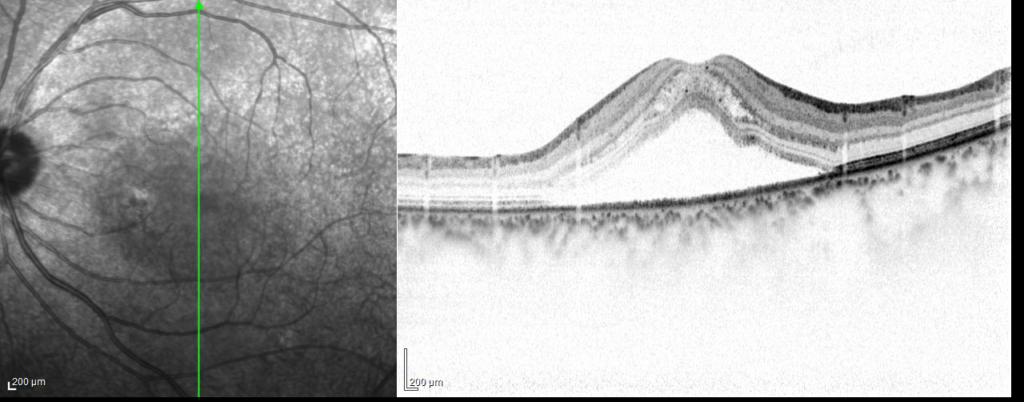

漿液性網膜剥離が見れら、網膜下に小さな色素上皮の隆起病巣がみられる。その周囲にフィブリンを示す中等度反射がみられる。網膜分離も伴っている。